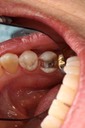

Larry Fujioka #12-12 caries removal

Larry Fujioka #11-12 caries removal